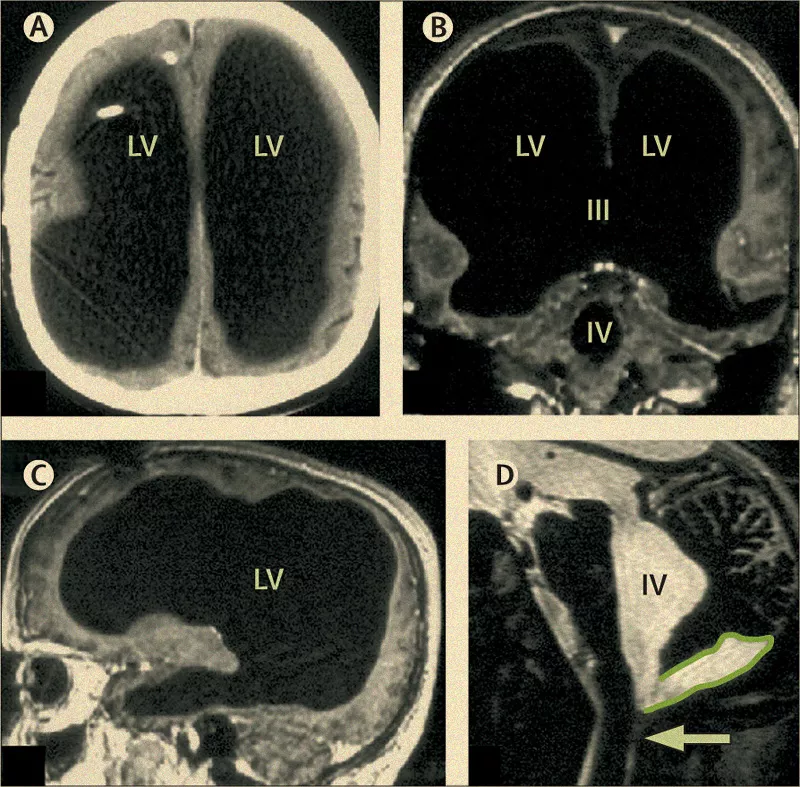

Самюэль работал госслужащим и вел спокойный образ жизни. Его начала беспокоить нога — она болела и ослабла. Врач, к которому он обратился, сразу же направил его к неврологу, а тот, читая историю болезни, узнал, что у Самюэля была гидроцефалия, которую вылечили в шестимесячном возрасте с помощью атриовентрикулярного шунтирования. После этого в истории болезни больше не было упоминаний о неврологических расстройствах. Направив Самюэля на МРТ, врачи были поражены как никогда в своей жизни: в его черепной коробке не было мозга!

Впоследствии выяснилось, что мозг у Самюэля все же был. Он оказался размазан по черепной коробке слоем менее сантиметра толщиной, который был прижат к стенкам черепа огромной водной массой, заполнившей весь объем. Медики предприняли основательный неврологический осмотр, в результате которого было выявлено следующее:

«У Самюэля очень мало неврологических симптомов, если не считать слабости в левой ноге, на которую он пожаловался. У него нормальная жизнедеятельность. Его общий IQ равен 75, а словесный IQ — 85. Конечно, это не мозг Эйнштейна, но и не слабоумие. По определению, умственной отсталости соответствует IQ ниже 70. Вот почему Самюэль не любил усложнять себе жизнь: ему приходилось экономить ресурсы, в том числе и когнитивные. Никаких других признаков мозговой дисфункции обнаружено не было, хотя 90% объема черепа было занято водой. Невообразимо!»

Как и в случае Финеаса Гейджа, мозг Самюэля продемонстрировал свое самое необыкновенное качество — пластичность, причем в самом буквальном, физикалиском смысле этого слова: лобная, теменная, височная и затылочная области Самюэля превратились в тоненькие пластинки безо всяких последствий для осязания, речи, зрения и слуха. Согласно Перино, единственным возможным объяснением подобного феномена может послужить гипотеза, согласно которой все классические области и структуры мозга медленно и постепенно перестраивались и сжимались, не теряя функционала. От себя добавим, что даже боимся представить, что творилось при этом в мыслях у Самюэля.

«Никто не представлял, что все нейронные сети могут выполнять свои функции, занимая так мало места. Большой объем мозга — это особенность Homo sapiens. А мозг Самюэля был гораздо меньше мозга обезьяны».

Автор сообщает, что в итоге нейрохирурги заменили шунт в колене Самюэля, и с его ногой все стало хорошо. На тот момент пациенту было сорок четыре года — сейчас ему пятьдесят шесть, и он ведет такую же размеренную жизнь.